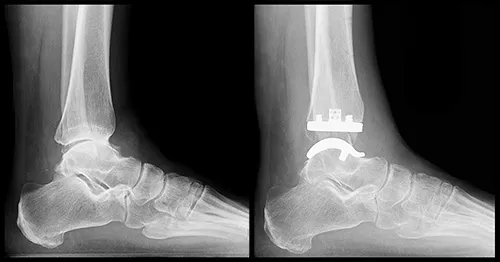

- Operative: Arthrodesis (fusion - gold standard for ankle), arthroplasty (joint replacement - for selected cases, e.g., 1st MTPJ).

- Total Ankle Arthroplasty (TAA): Motion-sparing for select isolated ankle OA.